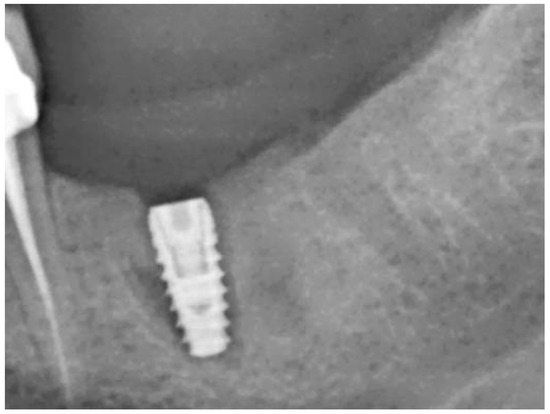

| Case No. | Sex | Age | Regio (FDA): | Reason for Tooth Loss: | Integration Period of the Graft: | Smoking Behavior: | General Medical History: |

|---|---|---|---|---|---|---|---|

| 1 | m | 42 | 25 | fracture | 130 | never | no abnormal medical history |

| 2 | m | 63 | 17 | endodontic | 319 | 10 cig./d | no abnormal medical history |

| 3 | m | 45 | 25 | unrestorable | 133 | never | no abnormal medical history |

| 4 | f | 77 | 36 | fracture | 207 | former smoker | type 2 diabetes, medicated |

| 5 | f | 62 | 46 | endodontic | 190 | never | no abnormal medical history |

| 6 | m | 54 | 37 | endodontic | 253 | former smoker | type 2 diabetes, medicated |

| 7 | m | 55 | 37 | tooth tilting | 292 | never | atopic individual |

| 8 | f | 43 | 26 | endodontic | 187 | former smoker | no abnormal medical history |

| 9 | m | 45 | 25 | unrestorable | 146 | former smoker | atopic individual |

| 10 | f | 44 | 15 | endodontic | 184 | never | no abnormal medical history |